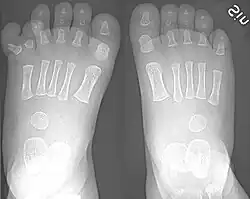

There are normally five toes present on each human foot. Each toe consists of three phalanx bones, the proximal, middle, and distal, with the exception of the big toe (Latin: hallux). For a minority of people, the little toe also is missing a middle bone. The hallux only contains two phalanx bones, the proximal and distal. The joints between each phalanx are the interphalangeal joints. The proximal phalanx bone of each toe articulates with the metatarsal bone of the foot at the metatarsophalangeal joint. Each toe is surrounded by skin, and present on all five toes is a toenail.

Humans usually have five toes on each foot. When more than five toes are present, this is known as polydactyly. Other variants may include syndactyly or arachnodactyly. Forefoot shape, including toe shape, exhibits significant variation among people; these differences can be measured and have been statistically correlated with ethnicity.[3] Such deviations may affect comfort and fit for various shoe types. Research conducted for the U.S. Army indicated that larger feet may still have smaller arches, toe length, and toe-breadth.[4]